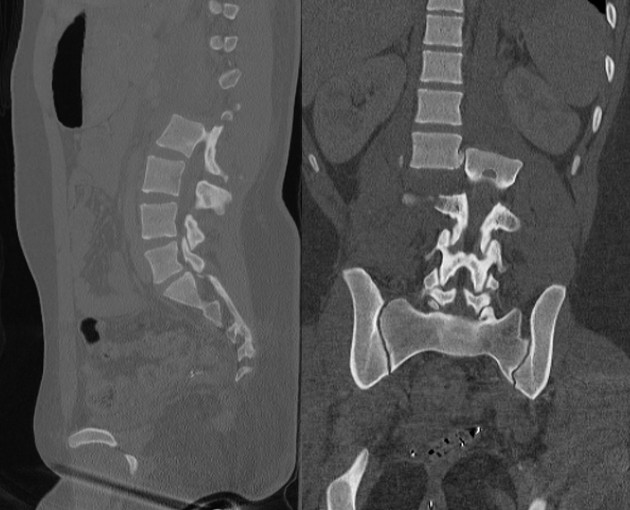

AO Type C fracture-dislocation — CT sagittal and coronal showing complete translational displacement of the spinal column

Type C — fracture-dislocation; complete translational instability